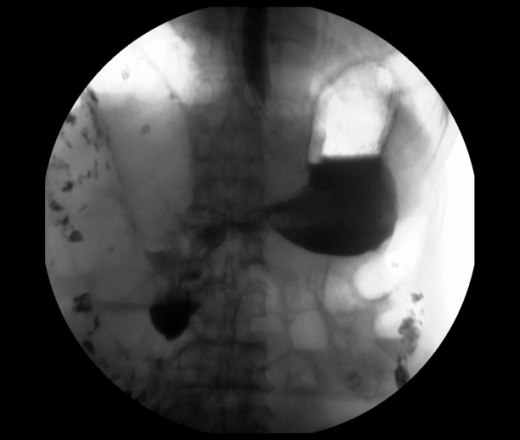

Мужчина 73 года. Жалобы на сниженный аппетит, слабость. Исследование выполенено через несколько дней после ирригоскопии. По результатам ЭФГДС гастрит.

Угол желудка развернут, ригиден. Стойкое циркулярное сужение антрального отдела.Перистальтики нет. Складки прослеживаются.

Эндофитный C-r антрального отдела.